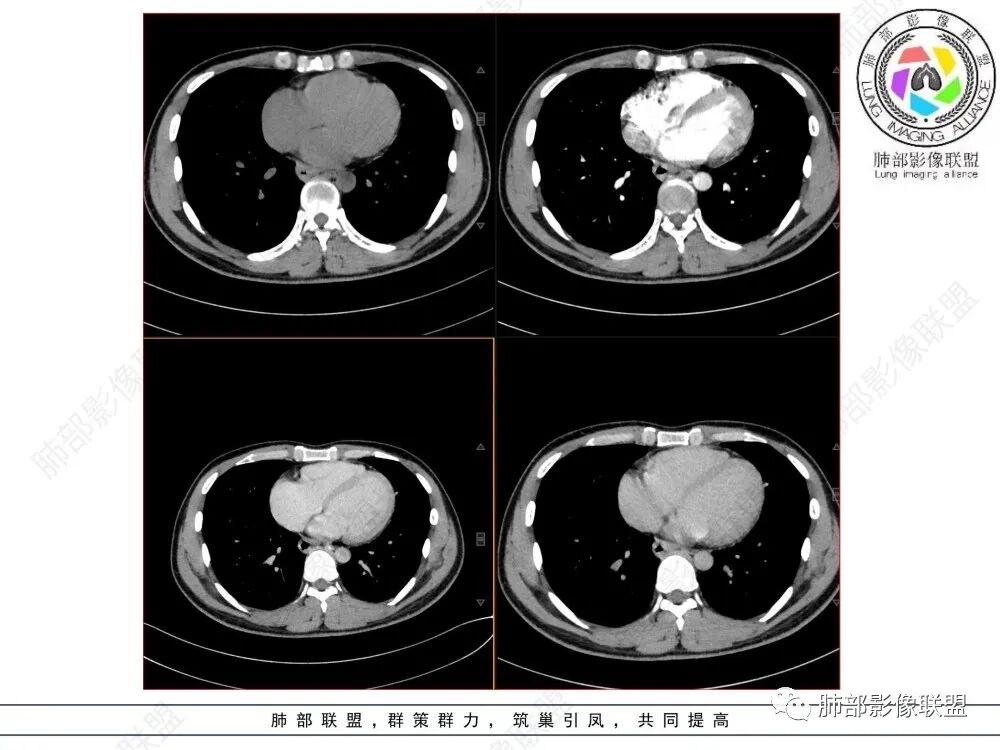

青年人,食管来源肿瘤性病变,平扫密度均质,病灶边缘分叶,食管部分僵硬,增强病灶轻中度强化,强化不愠不火,考虑恶性,淋巴瘤,鉴别食管平滑肌瘤,间质瘤。

食管下段近贲门处肿块,食道受压变窄,粘膜无破坏,轻度强化,T2等低信号,考虑平滑肌瘤?神经鞘瘤?鉴别间质瘤。

年轻男性,食管下段占位性病变长轴平行于食管,平扫密度尚均匀,增强轻度强化,MRI示T1、T2低信号,DWI低信号。考虑来源于食管,考虑平滑肌瘤或神经鞘瘤>间质瘤

平滑肌瘤(食管下段团块状肿块,环食管生长,分叶密度均匀,增强轻度强化。钡餐时食管受压移位,T1 T2 DWi低信号,病变来源于食管,考虑平滑肌瘤)

食管下段后壁团块状肿块,管腔受压,密度均匀,增强轻度强化,食管受压移位,考虑平滑肌瘤,鉴别间质瘤。

食管下段肿块,管腔受压变窄,密度均匀,增强轻度延迟强化,考虑平滑肌瘤,鉴别间质瘤。

影像学特点:类纵隔区病变,沿食管生长,形态不规则,但边界清楚,内部信号/密度均匀,强化程度比较弱。

影像诊断思路:起源食管肿瘤(非黏膜起源,肌层起源),良性或低度恶性肿瘤可能性大,一般以神经鞘瘤、胃肠间质瘤及平滑肌瘤为主。食管神经鞘瘤强化明显均匀、以食管上段多见,周围常见炎性增大淋巴结,不太符合;胃肠间质瘤小的比较均匀,大的不均匀,但强化程度较高;影像上看这例病例比较符合平滑肌瘤。

食管平滑肌瘤是最常见的食管良性肿瘤,多见于男性,男女之比为2.6:1,高发年龄 30~60岁之间与食管癌相比,食管平滑肌瘤 的一个主要特点是病史相对较长,病情进展缓慢。病史最长者达10年余,平均 15.7个月,尽管病史较长,但大多数患者仍能进普食。食管平滑肌瘤的诊断一般比较容易,结合患者临床症状、食管造影及食管镜所见,一般均能得出正确诊断。食管造影主要为充盈缺损,病变与食管壁成锐角,粘膜线连续无破坏,管腔收缩扩张比较自如。钡餐造影敏感性高,但对食管壁间及食管周围情况难以判断。CT具有极高的密度分辨率,并且可以获得高质量的多平面重组图像,有利于食管壁间及食管周围情况的判断,表现为食管下段环绕管壁生长,偏心性或薄厚不均软组织密度肿块,密度均匀,内缘分叶状,管腔与正常食管壁构成不规则多角形扩张,增强动脉期无强化,多角度重建其病灶长轴与食管长轴不一致。由于食管壁在收缩状态下厚度约为5.6mm,扩张状态厚度不超过3mm,CT扫描时保持食管处于扩张状态可提高小病灶检出率。MR表现为T1加权等信号,T2加权稍高信号,可见高信号粘膜层,增强扫描轻度渐进性强化,密度均匀,无出血坏死。对于粘膜及周围脂肪间隙的判断具有明显优势。